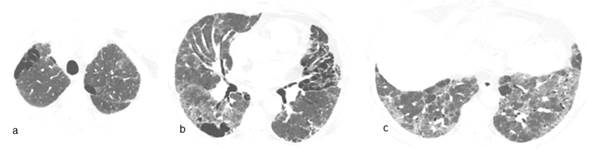

Varón 21 años, funcionario público, fuma 5 cajas/año, niega consumo de sustancias ilícitas, es traído a sala de urgencias por dolor agudo en hemitórax derecho acompañado de disnea intensa. Se constata neumotórax del lado derecho (Figura 3) que evoluciona favorablemente con drenaje pleural sellado bajo agua. Antecedente de cuadro similar un año atrás. Las imágenes sugieren el diagnóstico de histiocitosis de células de Langerhans. Se inicia tratamiento anti tabáquico (bupropión, terapia sustitutiva con nicotina y abordaje conductual).

La histiocitosis de células de Langerhans es una enfermedad de origen desconocido categorizada en formas localizadas (afecta hueso, piel y pulmón) y formas sistémicas. También se la conoce como histocitosis x o granuloma eosinofílico. El compromiso pulmonar exclusivo se suele ver en varones fumadores en los cuales la acumulación de las células de Langerhans en granulomas bronquiolocéntricos podría ser una respuesta reactiva (clonal o neoplásica) a algún agente aún no identificado18. Estos granulomas son expresión de la fase precoz, pues en las fases posteriores aparecen los difusos quistes con paredes finas, cuya ruptura explica que el neumotórax sea la primera manifestación de la enfermedad en 50% de las veces, como se constata en el tercer caso narrado aquí19. La TACAR ha reducido la necesidad de confirmación histopatológica y muestra que las lesiones asientan preferencialmente en regiones pulmonares medias o superiores. Las imágenes varían según la evolución de la enfermedad, predominando los nódulos o nódulos cavitados en estadios precoces y los quistes característicos en etapas tardías20.

La historia natural de la enfermedad es impredecible ya que puede retroceder en 25% de los casos, permaneciendo estable en su expresión clínica y radiológica en 50% y progresar hacia una forma destructiva extensa en los otros 25%21. El abandono del hábito tabáquico es prioritario en el manejo. Se reporta la utilidad de corticoterapia o el uso de cladribina (antimetabolito análogo de las purinas) en algunos casos. En casos avanzados hay que tener en cuenta la posibilidad del trasplante pulmonar22.